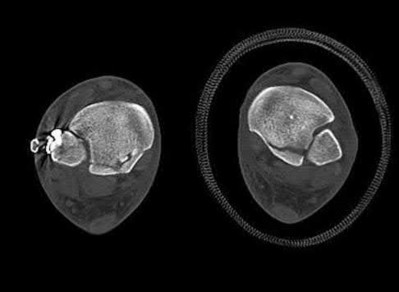

Figure 28 is the lateral radiograph of a patient who sustained an intra-articular fracture of the calcaneus. The structure (*) depicted by the arrows most likely represents which osseous component of the calcaneus?

Lateral portion of the posterior facet Corrent answer: 5

Fractures of the calcaneus occur as a result of shear and compression forces. Foot position at the time of impact, the force of the impact, and bone quality all dictate the degree of comminution and fracture line orientation. Two primary fracture lines are consistently observed, one of which divides the calcaneus into medial and lateral portions. An essential feature of this fracture

line is that it creates a fragment (sustentaculum tali) that remains attached to the talus by the interosseous ligament. This medial portion (constant fragment) of the posterior facet retains its normal anatomic position beneath the posterior talus. Its corresponding lateral component (labeled with an * in the figure), however, can be found displaced inferiorly within the body of the calcaneus. It is often rotated 90 degrees (as depicted in Figure 28) in relation to the remainder of the subtalar joint. This gives the appearance of what has been described as the "double-density" sign. The middle facet is more anterior and less commonly displaced. The lateral wall is nonarticular.